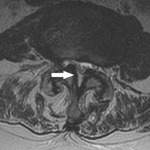

Visualização axial de um corpo vertebral mostrando estenose do canal vertebral

BMJ 2008;337:a2718; usado com permissão